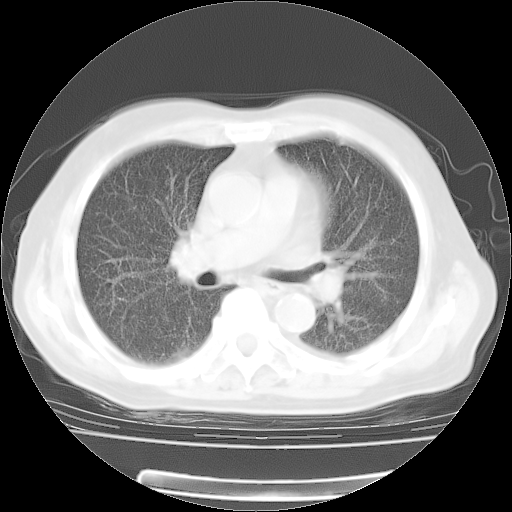

4月28日肺部CT

个人阅读4.14日肺部CT平扫:纵隔窗无异常,但肺窗示:双下肺内、后基底段有片絮状侵润影,部位以后基底段为著,以间质改变为主,呈急性肺泡炎征像,和首次住院影像学有相似之处。仅是个人读片,明日请相关专家再读片哈。其它建议同上。

今请临免主任会诊后认为:4月14日胸部CT已有双下肺间质性改变。患者病情复发多系激素减量过快不正规所致。目前甲强龙80mg/日,一周后酌情开始减量,不易过快。环磷酰胺若已停用,暂不使用。他同意目前抗菌药物使用,但应考虑是否加用B-内酰胺类抗菌药物(中性细胞明显增高);2、结核复发目前依据不足;3、若免疫全套各项指标正常,考虑多系特发性肺间质炎可能大。4、加强支持,并注意保护胃黏膜。